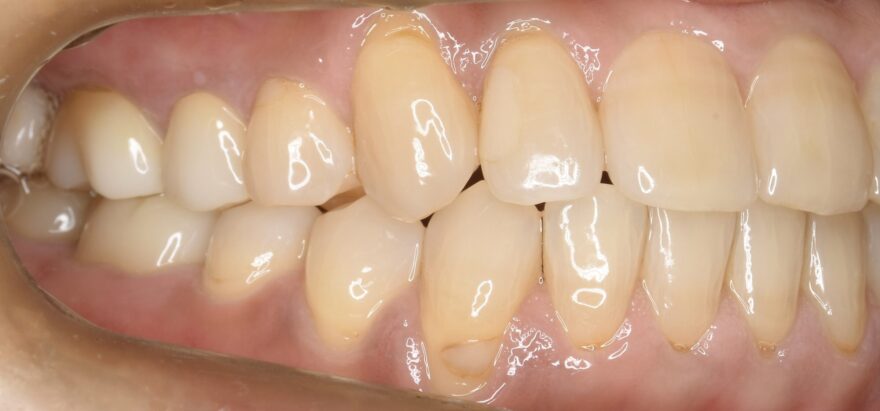

治療後の口腔内写真

なお前歯には、後戻り防止のためのワイヤーを装着しています。

右上の八重歯が気になります。